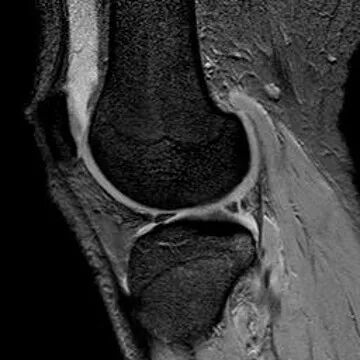

半月板纵行撕裂

1、纵行撕裂2、撕裂方向和半月板长轴方向平行3、垂直或斜行的III级高信号

(半月板纵行撕裂)